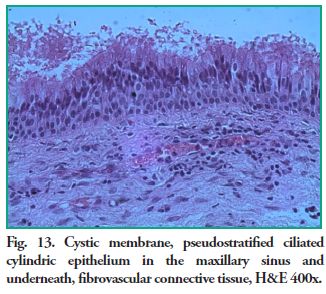

Microscopic description: Cystic cavity lined by a thin membrane made up of pseudostratified ciliated cylindrical epithelium (sinus mucosa), alternating with areas of hyperplasia, supported by fibrous connective tissue, with areas of edema, with plenty of capillaries, some of which are congestive and mixed inflammatory exudates. The content is amorphous and eosinophilic with inflammatory cells (lymphocytes and plasma cells) scattered in mucous material (Figs. 12 and 13).

Microscopic description: Cystic cavity lined by a thin membrane made up of pseudostratified ciliated cylindrical epithelium (sinus mucosa), alternating with areas of hyperplasia, supported by fibrous connective tissue, with areas of edema, with plenty of capillaries, some of which are congestive and mixed inflammatory exudates. The content is amorphous and eosinophilic with inflammatory cells (lymphocytes and plasma cells) scattered in mucous material (Figs. 12 and 13).